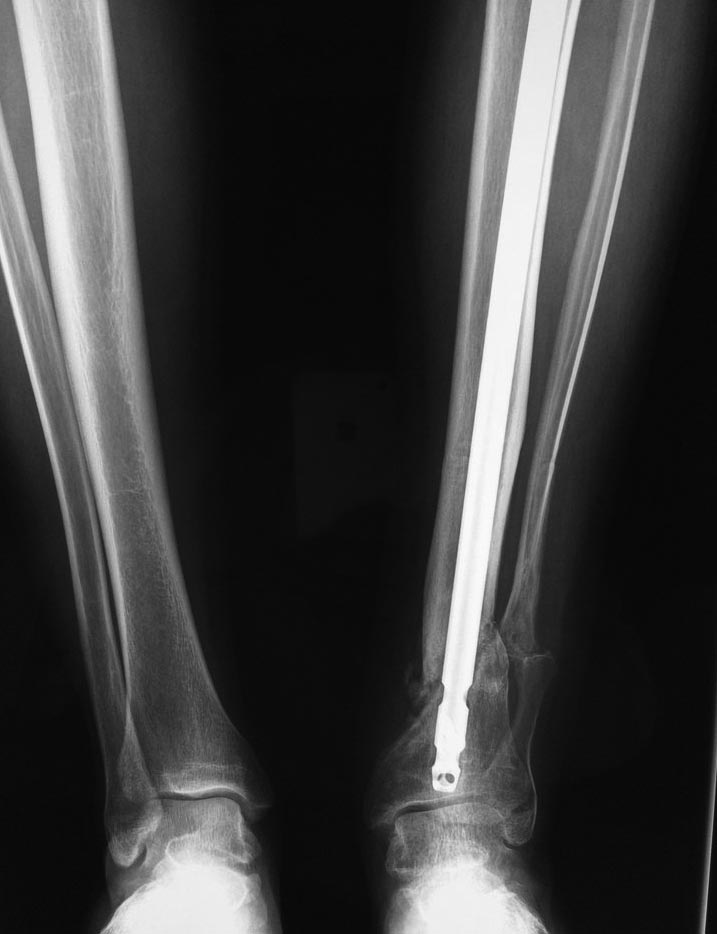

Через 6 мес. контроль - линия ложного сустава прослеживается, но имеется

периостальная костная мозоль.

Не хватает стабильности.

Вопрос что делать?